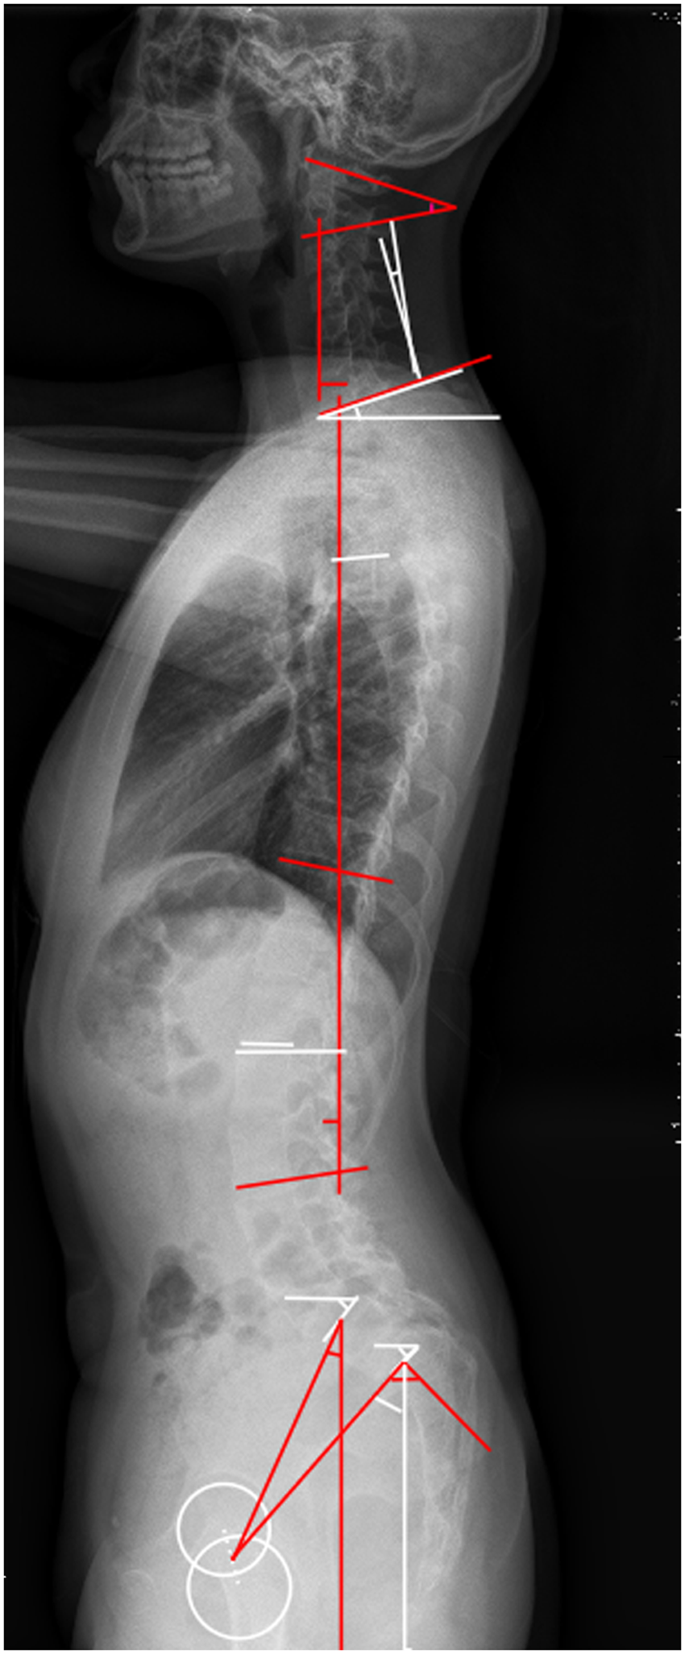

Demographic details on age, height, weight, BMI, and gender were collected. The radiographic films were measured independently by two researchers. The parameters measured were as follows:

Cervical sagittal alignment parameters: C1-C2 (C1-C2 cervical lordosis, the angle between C1 and the caudal endplate of C2), CL (C2-C7 cervical lordosis is the angle between the caudal endplate of C2 and the caudal endplate of C7), cSVA(cSVA is the horizontal offset from the plumbline dropped from C2 to the posterosuperior corner of C7), TS-CL (T1 Slope minus CL is the difference between T1 Slope and CL) (Fig. 2).

Thoracic kyphosis and Lumbar lordosis parameters: TK (thoracic kyphosis)30,31, LL (lumbar lordosis)30,31, TLK (thoracolumbar kyphosis).

Sagittal lumbosacral parameters: SS, PT, PI, L5 Slope(the angle between a horizontal line and the superior end plate of L5), and L5I (L5 Incidence, the angle between the vertical line and the line connecting the center of the femoral heads axis to the center of the upper endplate of L523) (Fig. 3).

Global sagittal alignment parameters: SVA (the horizontal offset from the posterosuperior corner of S1 to the vertebral body of C7), and T1 Slope (the angle between a horizontal line and the superior end plate of T1).

Slip percentage was assessed in those lumbar isthmic spondylolisthesis patients32. Figure 4 demonstrated the measurement of slip percentage.